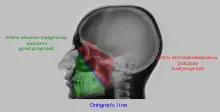

Onhgren's line

• Distance between antero-lateral wall of maxilla and coronoid process of the mandible is measured. If it is increased on one side, it indicates involvement of infratemporal fossa by the malignancy. This is called Handousa's sign. Prognosis of malignancy is determined by position of tumour on basis Onhgren's line.